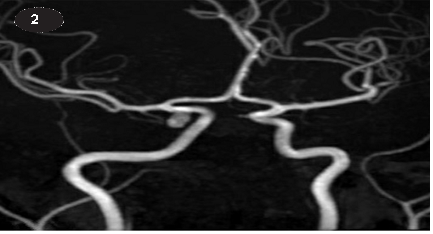

HÌNH ẢNH CHỤP CỘNG HƯỞNG TỪ

Phình động mạch thông sau PCCommA bên phải , KT: 6x3.8x3.6 mm